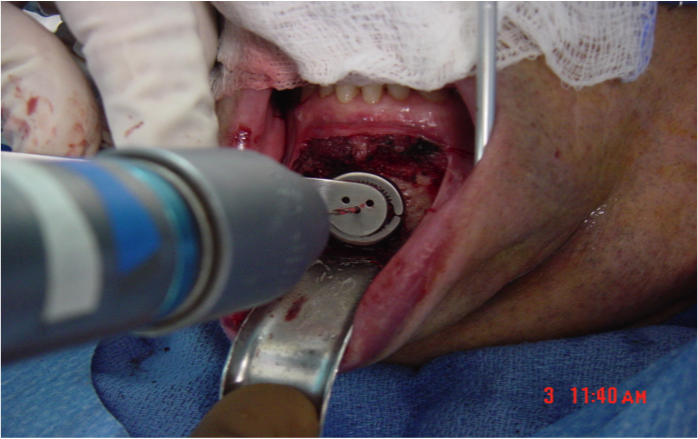

This procedure places tension on the tongue, limiting the posterior from shifting during sleep. The procedure starts with a small incision made inside the lower lip. Then, the surgeon moves away all the soft tissue to expose the lower jaw. Small rectangular cuts are then made in the lower jaw directly in front of the lower front teeth. This area attached to the genioglossus muscle is then moved forward and turned slightly. To hold this bone fragment in place, the surgeon puts in a titanium screw to immobilize it.

The photos on this website are from real surgeries performed by Dr. Ulloa. Due to the

graphic nature of the images and content, viewer discretion is advised.